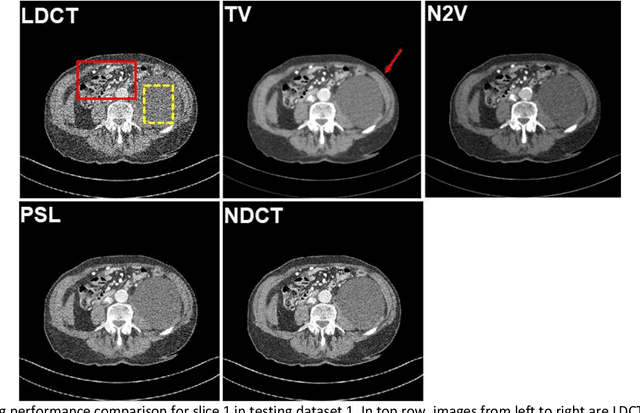

Abstract:Despite the indispensable role of X-ray computed tomography (CT) in diagnostic medicine field, the associated ionizing radiation is still a major concern considering that it may cause genetic and cancerous diseases. Decreasing the exposure can reduce the dose and hence the radiation-related risk, but will also induce higher quantum noise. Supervised deep learning can be used to train a neural network to denoise the low-dose CT (LDCT). However, its success requires massive pixel-wise paired LDCT and normal-dose CT (NDCT) images, which are rarely available in real practice. To alleviate this problem, in this paper, a shift-invariant property based neural network was devised to learn the inherent pixel correlations and also the noise distribution by only using the LDCT images, shaping into our probabilistic self-learning framework. Experimental results demonstrated that the proposed method outperformed the competitors, producing an enhanced LDCT image that has similar image style as the routine NDCT which is highly-preferable in clinic practice.